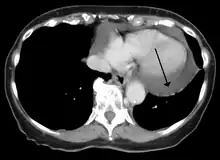

A CT scan showing a pericardial effusion

Pericardial effusion due to malignancy. Note bulbous heart and primary lung cancer in right upper lobe.